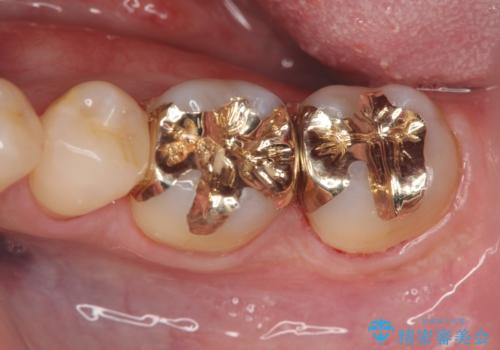

- 12万円 ゴールドインレー×2費用は治療当時の料金となります

ゴールドインレーについて

ゴールドは見た目に難がありますが、歯を削る量がセラミックに比べて少ない・複雑な形にも追従しやすい・壊れにくいなどの利点があります。